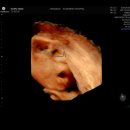

• 장성병원 | 전라남도 장성군 위내시경 전문 병원 후기 추천 6곳, 2026년에 알아보세요

전라남도 장성군에서 위내시경 전문 병원을 찾고 계신가요? 신뢰할 수 있는 병원 선택을 돕기 위해 추천 병원 후기 6곳을 소개합니다. 아래 내용을 참고하시기 바랍니다. 전라남도 장성군 위내시경 전문 병원 후기, 추천 6곳! - 프리미엄포스트 전라남도 장성군 위내시경 전문 병원 후기 좋은곳 추천 6곳 troawgzq.com...